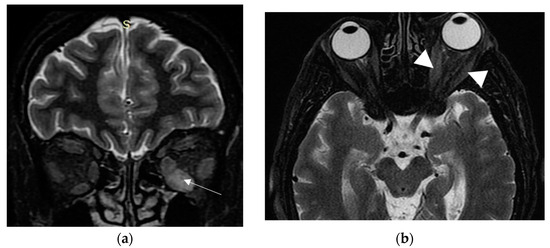

2. Case Presentation